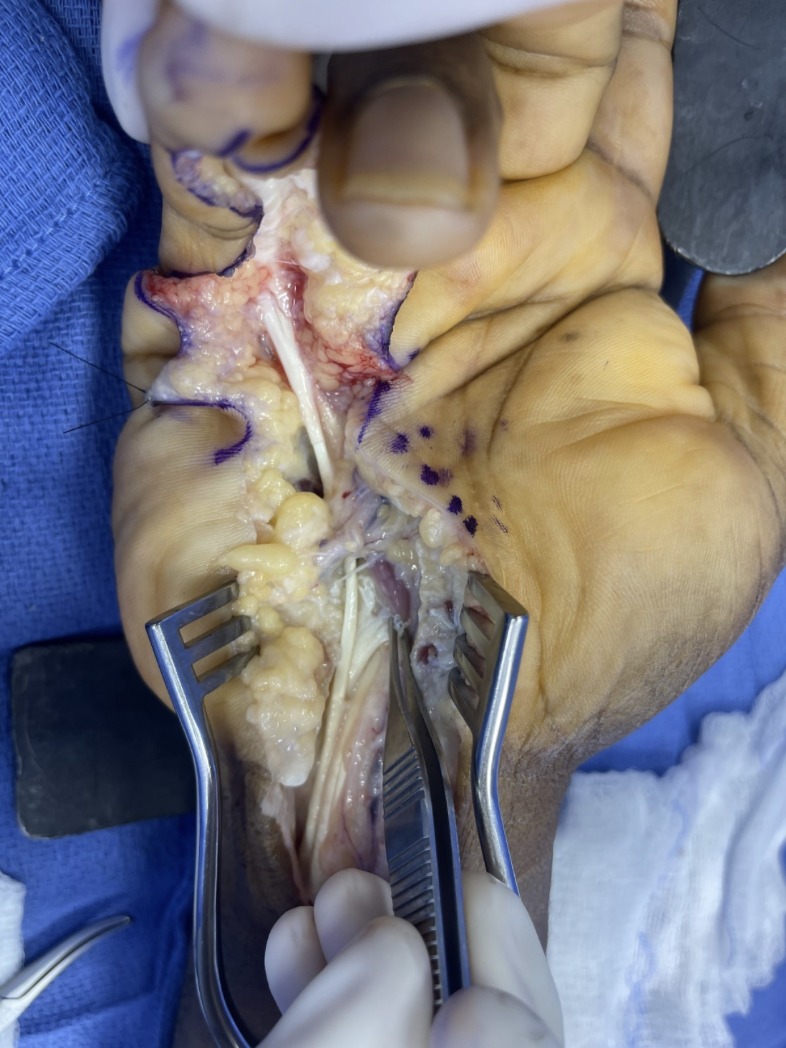

A 55-year-old, otherwise healthy, right-handed construction worker presented to the emergency department 2 days after an injury sustained while carrying a heavy piece of furniture. The furniture slipped in his hands, resulting in forced hyperextension of the metacarpophalangeal joints with flexion of the interphalangeal joints. There was an audible "pop" followed by immediate pain and swelling of the palm. On exam, he was unable to flex at the distal interphalangeal (DIP) joint. There were no wounds or lacerations, but there was a palpable mass over the ulnar aspect of the mid-palm. He had no nerve deficits. Radiographs were obtained, which demonstrated no fractures, dislocations, or arthrosis (Figure 1).

Figure 1. Three-view radiographs of the patient's right hand demonstrating no acute osseous abnormalities.